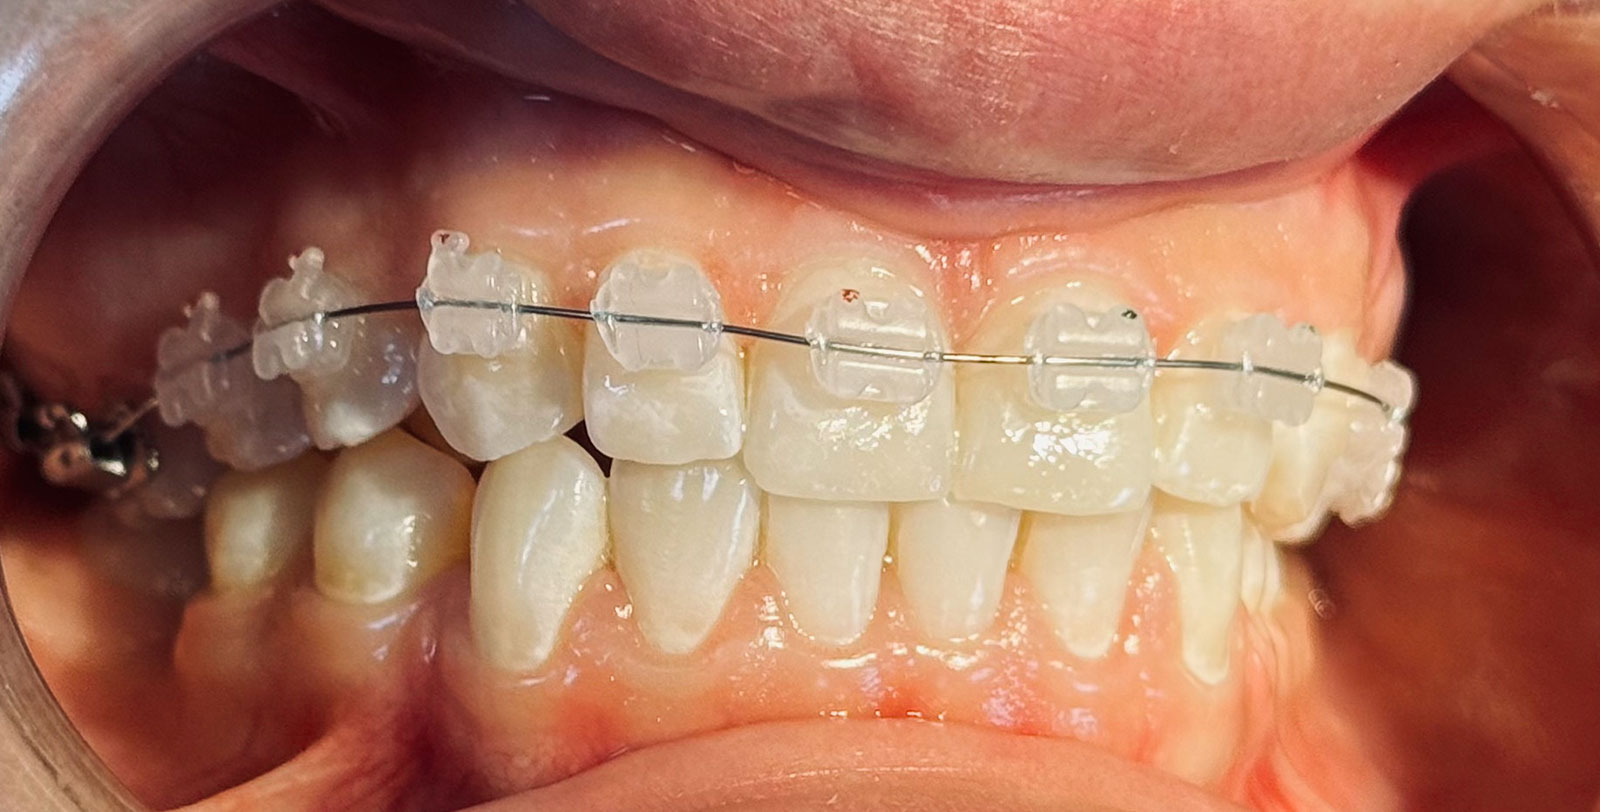

Керамічні брекети виглядають як емаль зубів, майже непомітні, тому це найпопулярніше рішення для корекції прикусу як у дорослих,так і у дітей.

Це один із видів ортодонтичних систем, які прикріплюються до передньої частини зубів і використовуються для корекції прикусу, випрямлення скручених, нахилених, криво зростаючих зубів, позбавлення від щілин між зубами та інших деформацій легкого та середнього ступеня тяжкості. З керамічними брекетами ви можете виправити прикус непомітно для оточення. Розгледіти на ваших зубах брекети можна тільки при дуже близькому контакті.

- Керамічні брекети білого кольору майже непомітні, мають міні розмір та мають властивості (хамелеону)